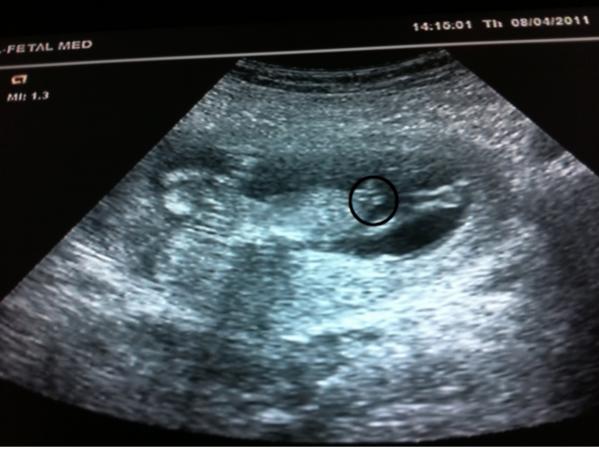

When I showed dh these pics he immediately pointed out what he was sure was a penis. Fast forward 7 wks and sure enough its a boy. Is this penis, was he right?

I think so, i mean it is definatly in that reigon.

I can see it as goodies or maybe just leg but dh was sure he saw "willie" lol

Looks like it might be cord.

Ooh never thought about the cord, that could definitely be cord!